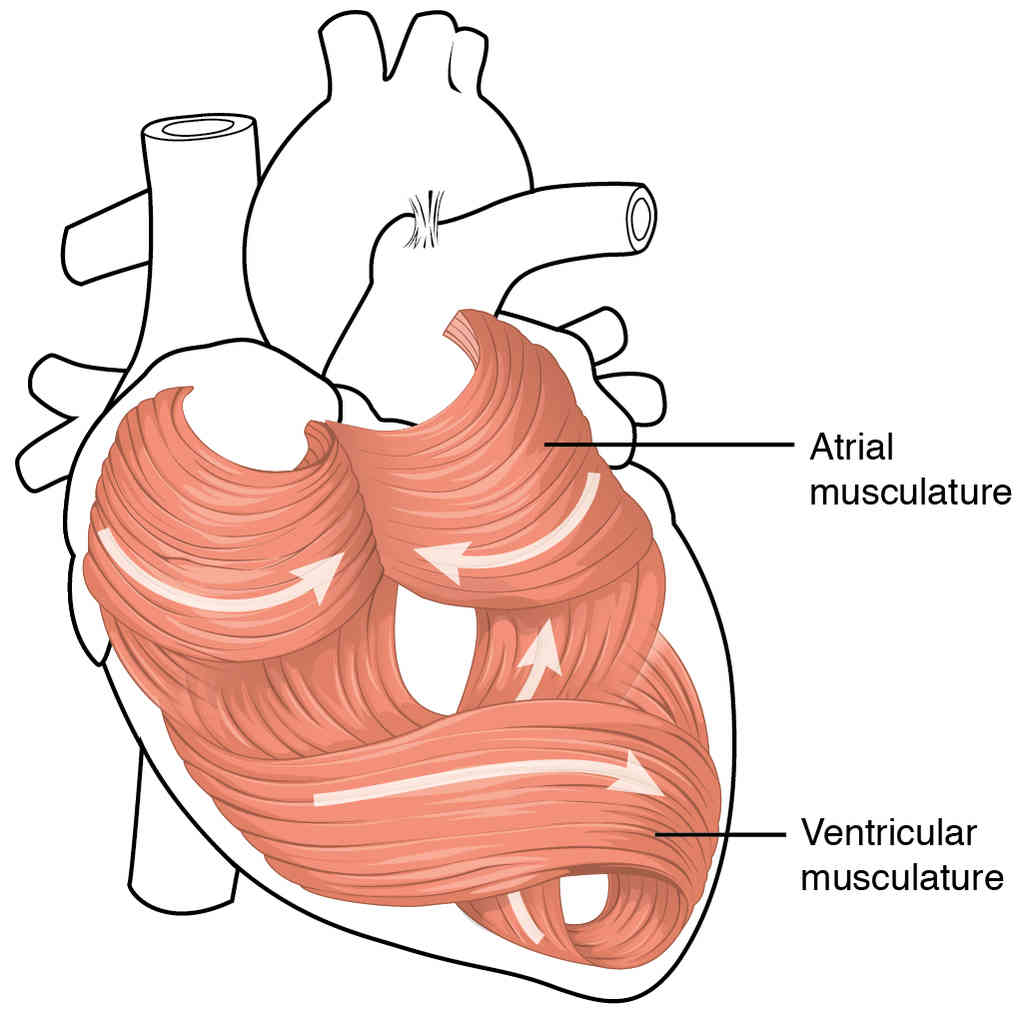

This page is under construction. For now, it is just a resource of the images found in the OpenStax Anatomy and Physiology Handbook. It wil slowly change into a revision tool. Each slide has a number. Use this to refer to the slide. When completed, it will have an unlabelled section, with labelled slides in parallel. On the unlabelled slides, write your answer and use the labelled slide to assess yourself. Keep track by also noting the number on each slide. Improvement at each attempt is important, more so than full marks on a first attempt.